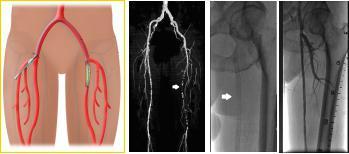

一旦疾病进入“静息痛”或者足坏疽阶段,应通过介入或手术打通闭塞的血管,恢复患肢的血供。

下肢动脉硬化性闭塞症的血管腔内介入治疗具有微创、操作简单、疗效确切、可重复操作的优点,是治疗下肢动脉硬化闭塞症的最佳选择。该方法经动脉穿刺,输送球囊导管至动脉狭窄或闭塞的部位,扩张、重建动脉管腔,结合血管腔内支架的使用,可获得较好的临床效果。